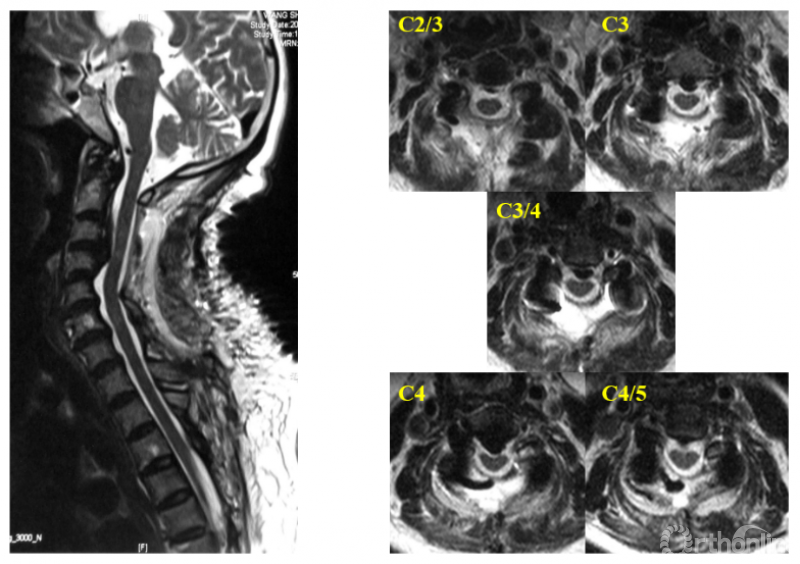

于是,我们回顾性分析了45例含上颈椎后路减压的压迫性颈脊髓病患者的临床资料,按减压范围分为C2-7组(25例)和C1-7组(20例)。利用本系列研究第三部分建立的方法,对两组各个节段的椎髓间距(VCD)进行测量和比较。与之前的研究不同的是,为了避免由于上颈椎形态不规则对测量造成的影响,将参数测量方法人为的标准化,称为标准化椎髓间距(standardized vertebral -cord distance, SVCD),并对测量位点进行了细化,增加了寰椎水平的数据(记为SVCD-C1)、枢椎齿突与枢椎椎体结合部的数据(记为SVCD-C1/2)、枢椎椎体中部水平的数据(记为SVCD-C2)(图1)。并对各个节段的SVCD进行组间比较。

图1

结果显示不仅在C1水平,C1-2及C2水平的SVCD在两组间也有显著差异(图2)。而在C2/3及以下节段,两组间均无显著差异。也就是说,在C2-7减压的基础上切除寰椎后弓,因此而减压效果获益的区域仅限于C1至C2椎体中部区域(图3),无助于C2/3及以下节段减压效果的提高。

图2

图3

通过正态性检验,我们还可以进一步估算两组在C1/2及C2水平致压物大小与压迫残留几率的关系,选择合理的临界值。在C1/2水平致压物矢状径为8.5mm时,C2-7减压在该水平压迫残留率为54.70%,C1-7减压在该水平压迫残留率降低至16.26%;C2水平致压物矢状径为8.5mm时,C2-7与C1-7减压在该水平压迫残留率分别为57.76%与28.82%。

寰椎后弓切除显著提高了颈后路手术在上述测量水平的减压效果。8.5mm可作为在C1/2和C2水平致压物矢状径的临界值。当致压物在C1/2或C2水平超过8.5mm时,即使在寰椎水平无脊髓受压,仍建议向头侧扩大减压切除寰椎后弓,以获得更好的减压效果。

当OPLL累及上颈椎时,需要权衡是否需要切除C1后弓的情况并不少见,本研究有助于合理确定寰椎后弓切除的指征。除了寰椎水平脊髓腹侧(如颈椎后纵韧带骨化延伸至寰椎前弓)或背侧(寰椎后弓发育不良或畸形)存在压迫这一常见手术指征,在寰椎至枢椎体中部范围内,当致压物的矢状径超过采用C2-7减压能获得的SVCD(8.5mm)时,向头端扩大减压,行寰椎后弓切除是获得充分减压的有效手段(图4)。

图4